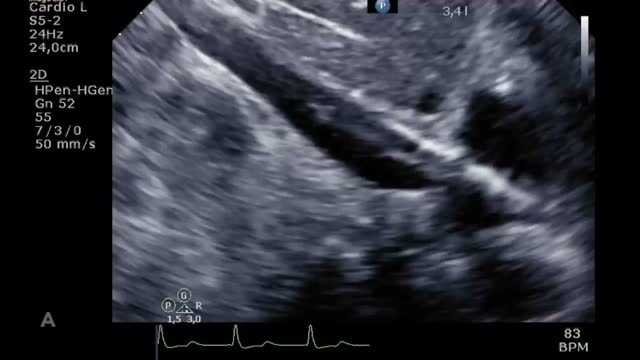

El destete supone un proceso de descenso gradual (500ml cada 15-20min) del soporte de la ECMO VA de manera que se restablece progresivamente la precarga en el corazón. Para ello el paciente debe estar adecuadamente anticoagulado. Evaluaremos la repercusión hemodinámica (PVC, PAM y diferencial, SvO2, SatO2) y ecocardiográfica (FEVI, IVT, onda E, onda E’ o S’ del anillo mitral lateral) que tiene hasta un nivel (normalmente 1-1,5l/min) que nos indique que el paciente puede tolerar la retirada de la asistencia. Durante esta, evaluaremos que mantiene e incluso aumenta la FEVI por encima del 25-30%, la IVT por encima de 10cm y la onda S’ de más de 6cm/s (fig. 5 y suplementario 22). Junto con ello, también evaluaremos el comportamiento de las cavidades derechas (desplazamiento sistólico del plano del anillo tricuspídeo>16cm, S’>10cm/s y tamaño VD) y la posible aparición de signos de hipertensión pulmonar (aumento de la velocidad pico de la insuficiencia tricuspídea) que predigan un fracaso de VD38–40.

Evaluación ecocardiográfica de destete de paciente con ECMO VA. Ecografía transtorácica e integral velocidad-tiempo (IVT) del tracto de salida del ventrículo izquierdo al reducir flujo (A: 3L/min, B: 2,5L/min, C: 2L/min) de ECMO VA. Obsérvese el aumento del tamaño de la IVT y consecuentemente del volumen sistólico y del gasto cardiaco.